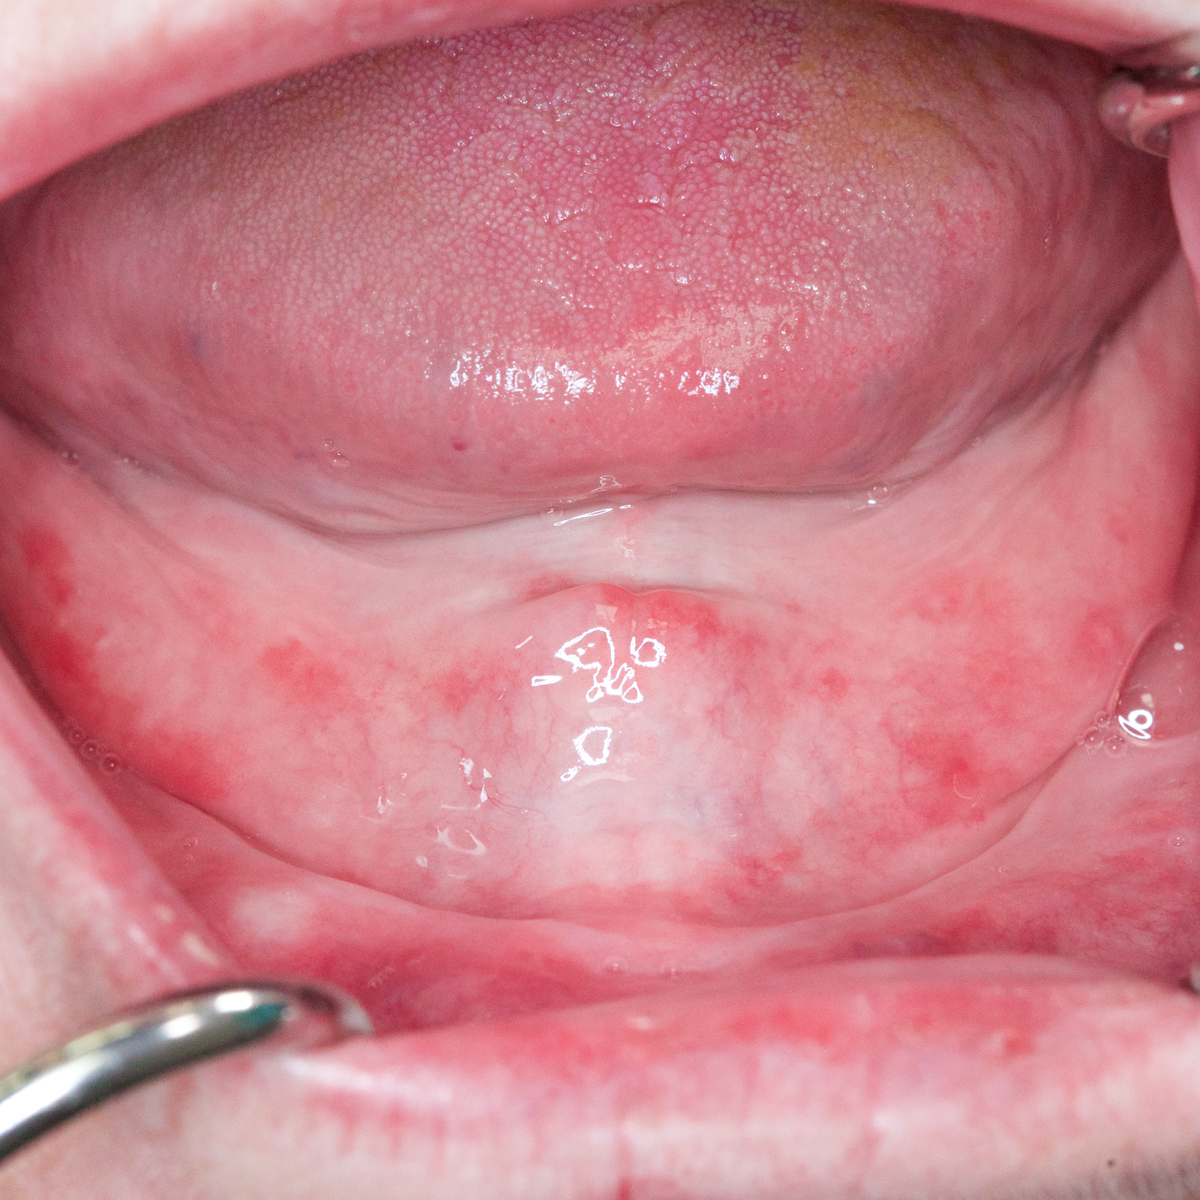

Unhealthy Denture Bearing Tissues

Continuous resorption and prosthetic tooth wear may lead to distortion of the surface contours of the residual ridge, which will ultimately result in poor tissue heath. Unhealthy or pathologic tissues are not able to withstand normal masticatory forces. Pathologic conditions worsen with the continuous use of dentures because they are accompanied by foreign bodies that further irritate the tissues. New dentures fabricated on abused or irritated tissues will exhibit reduced retention, lack of stability, and changing occlusal relationships.19 Therefore, the health and form of the denture supporting tissues must be optimized prior to the fabrication of new dentures. Tissue conditioning materials can be used to promote recovery of denture bearing soft tissues without having to ask patients to discontinue the use of their dentures.10

Prolonged usage of an old denture may lead to problems with flange extensions.4 Overextended flanges may result in tissue trauma (Figure 9). They must be relieved and adjusted appropriately, and the patient should be recalled regularly for evaluation.4 Prominent frenum attachments can prevent the development of an optimal border seal and may require surgical repositioning or removal.4 The presence of depressed irregularities, exostoses, tori, hypertrophic tuberosities, and significant undercut areas in the denture foundation should be noted. Surgical intervention should be considered for any defects expected to cause chronic soft tissue irritation, restrict normal function, prohibit optimal impression making, or interfere with proper denture border extensions (Figure 10).1,20,21

(9.) Epulus fissuratum.

Figure 9